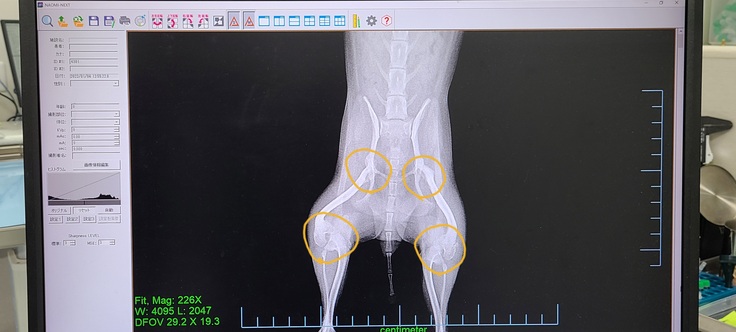

なぜ保護されているのか伺ったところ、先天性の膝蓋骨脱臼両足ともグレード4ということでした。まだ幼いのに処分されるなんて考えるとかわいそうで1匹でも命を救いたいという思いで家族に迎えました。

外科手術できる動物病院を探して受診しました。獣医師の診断では先天性両足の膝蓋骨脱臼グレード4と両足股関節形成不全という結果でした。手術をしても必ず歩けるようになる保証もないし、今のまま成長しても痛みが酷くなるのでほっておけないとのことです。

手術方法を伺うと、膝蓋骨脱臼のほうは成犬になるまでに大腿骨を数ヶ所切断して骨を調節し器具で繋ぎ留めるという想像しただけで怖い内容でした。